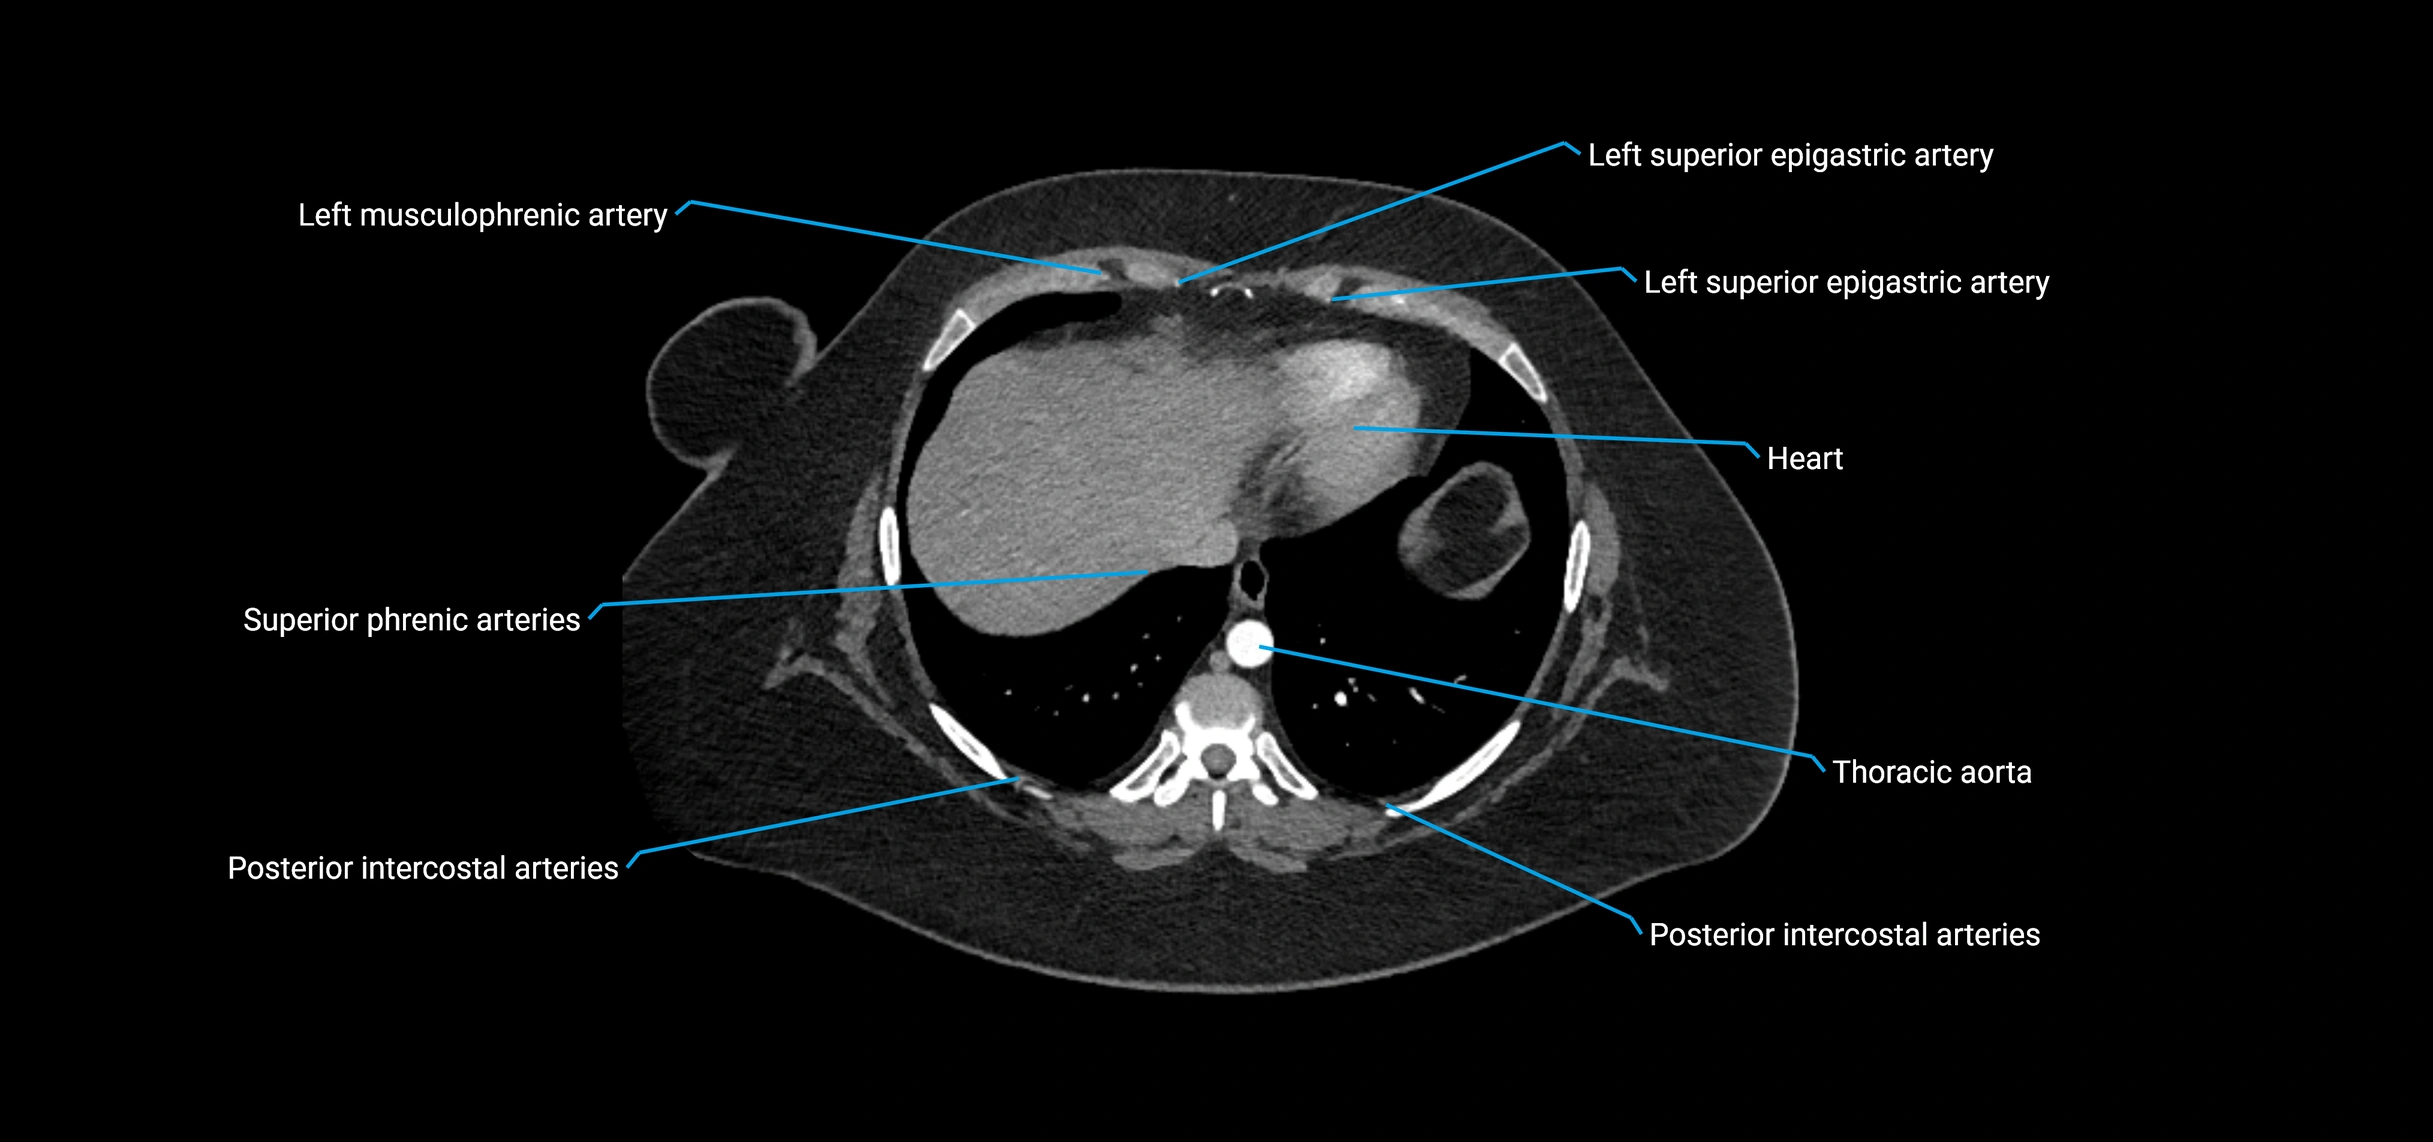

MRI images

image